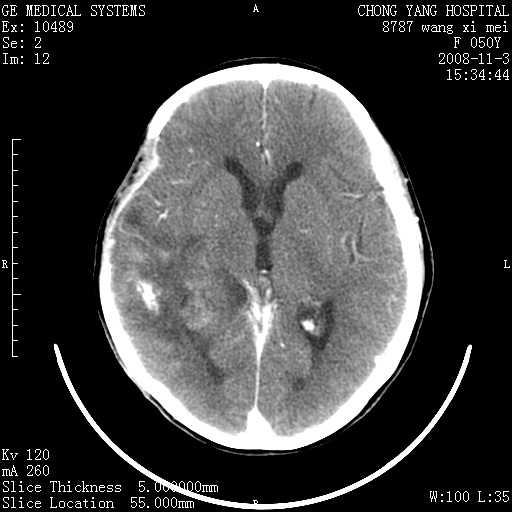

标题: CT16469:女,50岁,胶质瘤术后6年,今平扫加增强,请大家帮 [打印本页]

标题: CT16469:女,50岁,胶质瘤术后6年,今平扫加增强,请大家帮

右侧颞顶部可见低密度实变影,内见不规则钙化灶,边界不清,占位效应明显,侧脑室后角受压移位,符合胶质瘤术后复发改变。

右颞骨局限性缺如,局部脑组织无外隆。右颞叶可见片状脑脊液样低密度影,边缘较清,右侧侧脑室三角区可见一块状等密度影,且伴有强化,余未见明显异常改变。

考虑:右大脑术后改变伴肿瘤复发。

手术后局部片状低密度改变(软化灶),其后方颞叶似等密度病灶,界限不清,内见钙化,有轻度占位效应,但增强后强化之血管走行如常。应不考虑:复发!

考虑右侧颞顶叶胶质瘤术后复发。

应考虑肿瘤复发,右颞顶叶已出现轻度强化肿块.必要时可与原片比较以下.

右侧颞顶部混杂密度影,内有钙化,有占位效应。应该是复发灶。结合术后片更好。